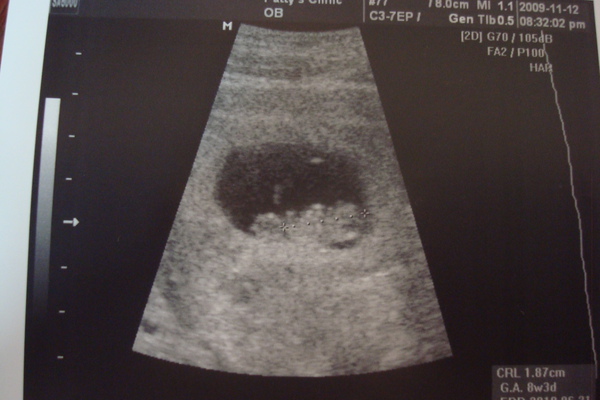

這是胎兒八周大的照片,距離第一次產檢約兩週的時間,

上次的超音波顯示胚胎為0。77cm

這一次則是1。87cm(於照片的右下角可見)

胚胎正常的長大中,並且已經稍微看得見頭與身體的區別

也有四個小點點的四肢出現了,只是不明顯。